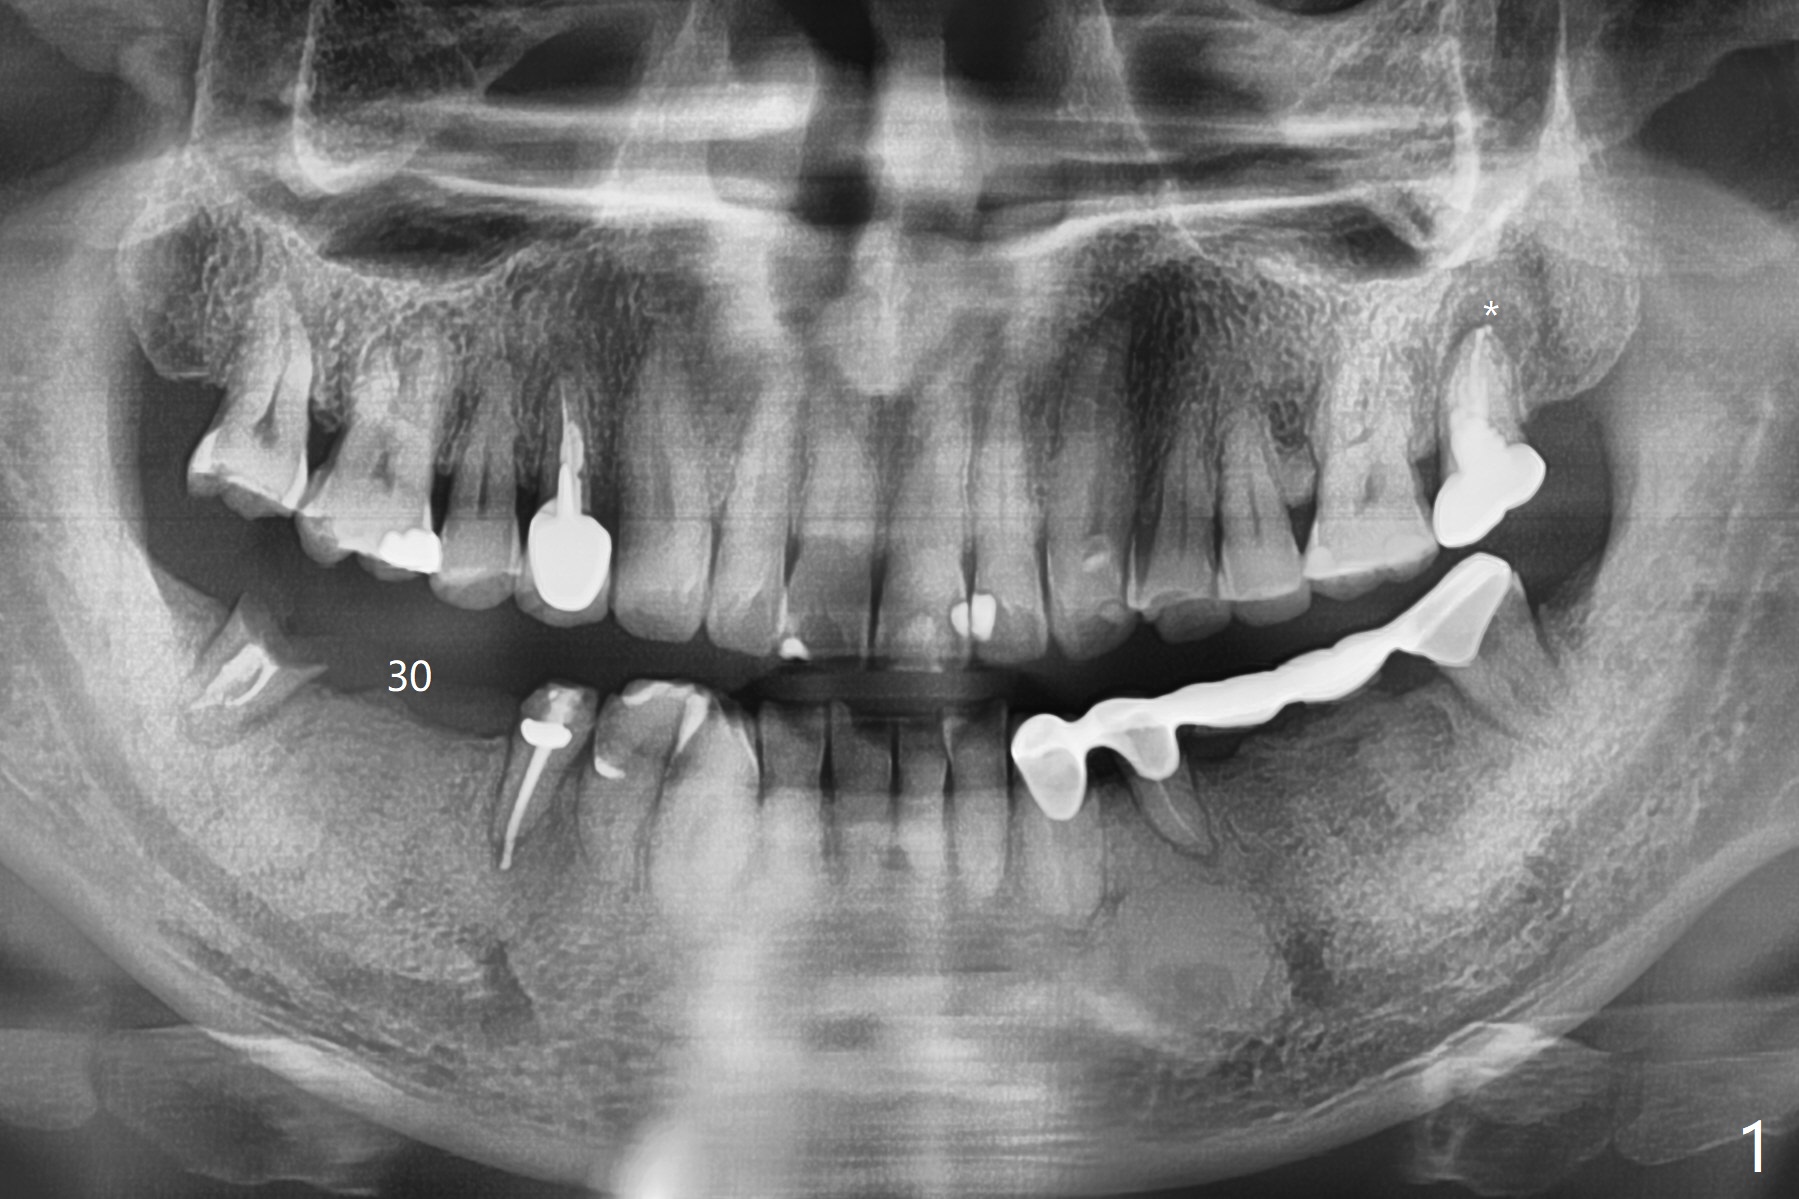

A 60-year-old man has lost a lower right FPD (Fig.1). The ridge at #30 is wide. To control implant spacing, PVS impression will be taken for guided surgery. Use the residual roots at #31 as a distal anchor tooth to finish implant placement at #30. After extraction, use implant anchor at #30 and finish implant placement at #31. Or 3-4 mm osteotomy will be initiated in the native bone using stopper for free hand (Fig.2 red line). An implant will be place ~ 1 mm subcrestal (green outline). Ask the lab to fabricate a stent for provisional with ~ 1 mm occlusal clearance.

My question is have you measured the how much remaining bones are left at the extraction socket. How much bone depth is left after the root extraction? Do you think the implant could get enough fixation after the extraction? Jennifer It is a good question. As today's CT indicates (07/30/2018), there is ~ 3 mm bone for primary stability with ~ 1 mm clearance (Fig.3-6). Because of the tapered implant, ~5 mm of the implant will be able to contact the native bone if the implant is lingually placed (Fig.6). If you feel it too much a risk, still make a guide for #31 so that an anchor pin can be placed at #31 residual roots for fixation (a new idea?). Make sure that the distal portion of the guide contacts the #31 residual root stump for stability, which is superior to a guide resting on the soft tissue. I have had experience placing implants free hand in this situation. The guide will be great help. I will use judgment in surgery. The worst scenario is socket preservation. Thanks for consideration and design.